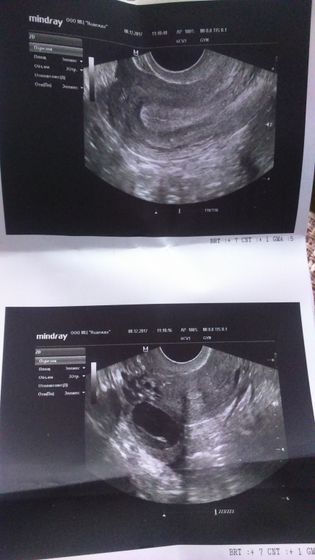

Ой привет девочки))) давно не заходила сюда. Столько новостей тут) зима пришла, я так ждала снега))) как ребенок радовалась)))я вот вчера была на УЗИ, посмотреть что там у меня. Тест был красивый на О, фото приложу. Пришла и расстроилась. Эндометрий 12 мм, а фолик 26 это уже переросток. Врач сказала что наврядли лопнет уже. Ну вот как так… Печально. Ну значит жду лапару 7 марта))))

Первый раз отслеживаю О фолликуламетрией, сегодня 19 дц из 30. Два ДФ 25 и 20. Думала хотя-бы одна лопнет, но нет. Назначили на УЗИ во вторник. Посмотрим что будет.